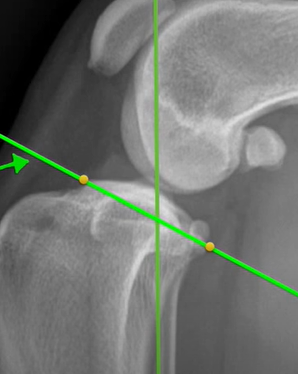

Functional Tibial line must be formed by connecting

The centre of intercondylar eminences shown in Fig. 1;

Following the identification of points of interests, and drawing of the lines of interest, i.e. the Functional Tibial Line (FTL) and the Medial Tibial Plateau Line (MTPL), another line is drawn such that the relation of new line and the FTL is 90°. Tibial plateau angle is the angle between this new line and the MTPL; this is shown in Fig. 3.